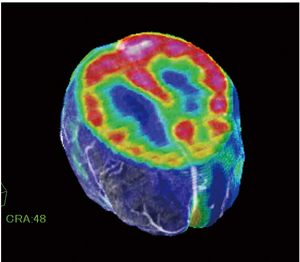

●Fusionソフトウェア

認知症を評価するモダリティはCT,MR,SPECTなど多数ありますが,それを同時に重ね合わせて観察することができるソフトウェアが“Fusionソフトウェア”です(図1)。

自動で位置合わせも行え,重ね合わせた画像の透過度も自由に変えられるため,そのモダリティの特長を最大限生かした画像診断が可能となるツールです。

図1 Fusionソフトウェア